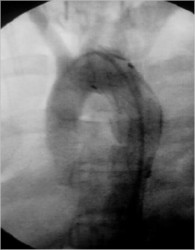

Endovascular Procedure

After Procedure

The outcome was excellent and the patient is in good shape rightnow with a normal lifestyle.